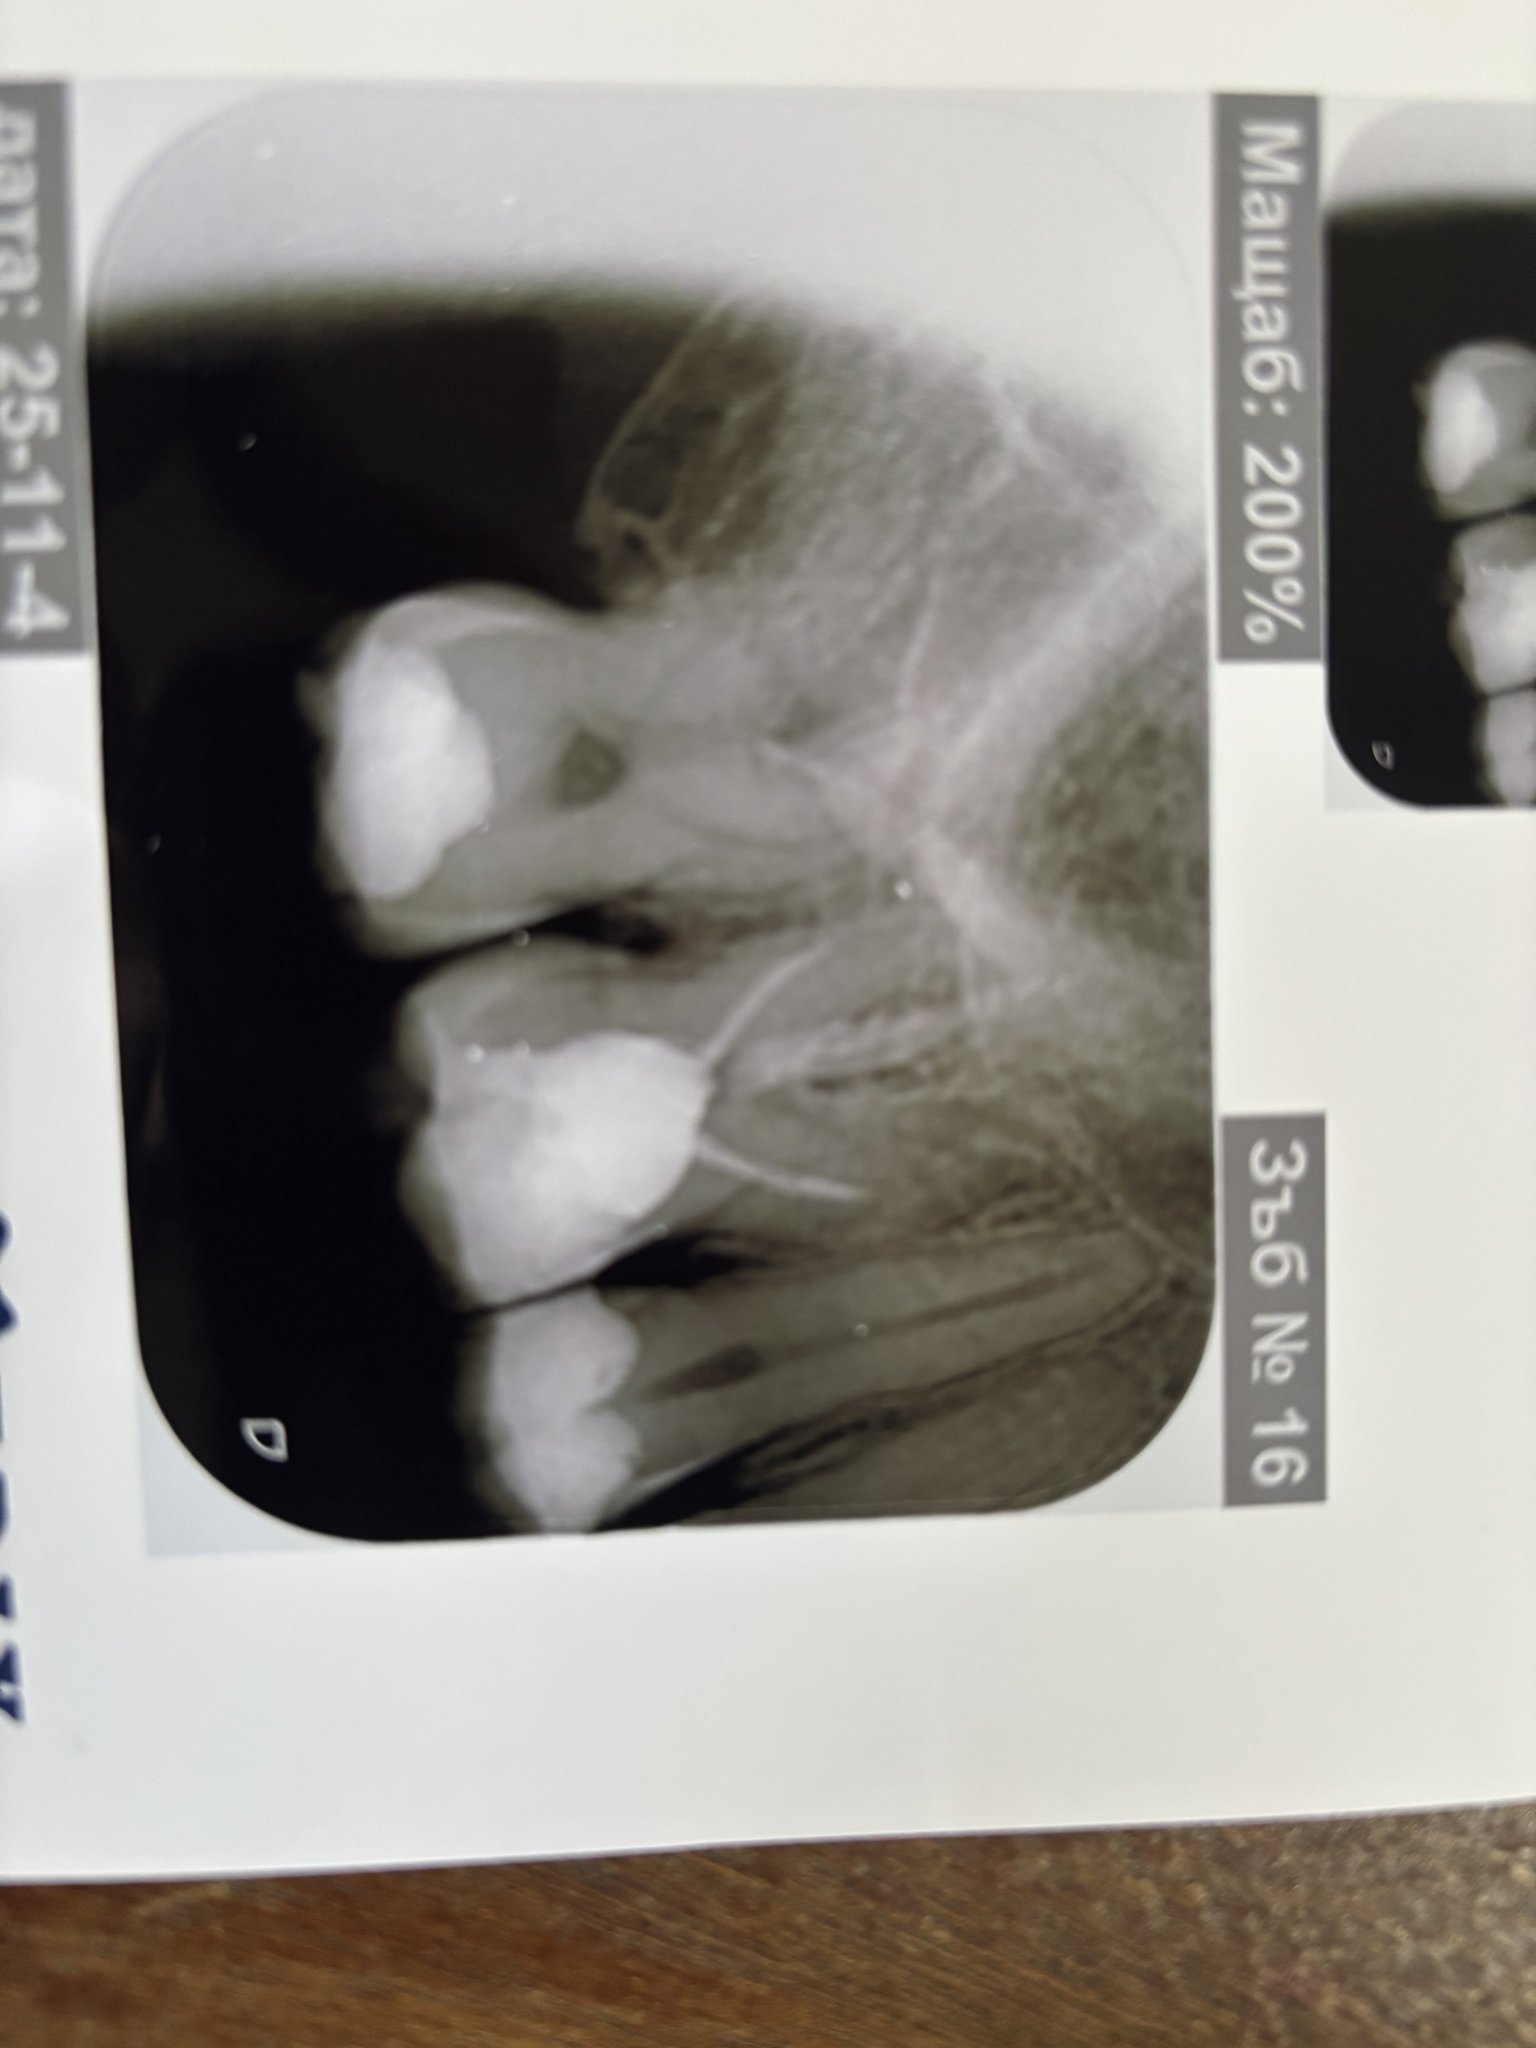

Касае се за пациент на 30г, зъбът е 6-ти горе-умъртвен преди 10г, без оплаквания досега. Имах КОВИД, с температура, запушен нос и много силна кашлица. Един от дните кашлях почти постоянно и докато кашлях усетих нещо като напрежение/ сърбеж в този зъб. Усетих го на няколко пъти, откакто оздравях не съм го усещал повече.

Направих снимка по препоръка на мой близък, предстои ми скоро преглед, но искам съвет. Има ли нещо нередно което се наблюдава

До Hroksi, добър ден. Извинявам се за късния отговор. Зъбът е с немного добре запълнени коренови канали. Те са затворени 1/3 от това, което трябва да бъде. От тази снимка не е ясно дали има патология. Чувствителността може да се дължи на самото заболяване от ковид, ако се е подула лигавицата на синуса. Надявам се да съм бил полезен. С уважение: д-р Маринов